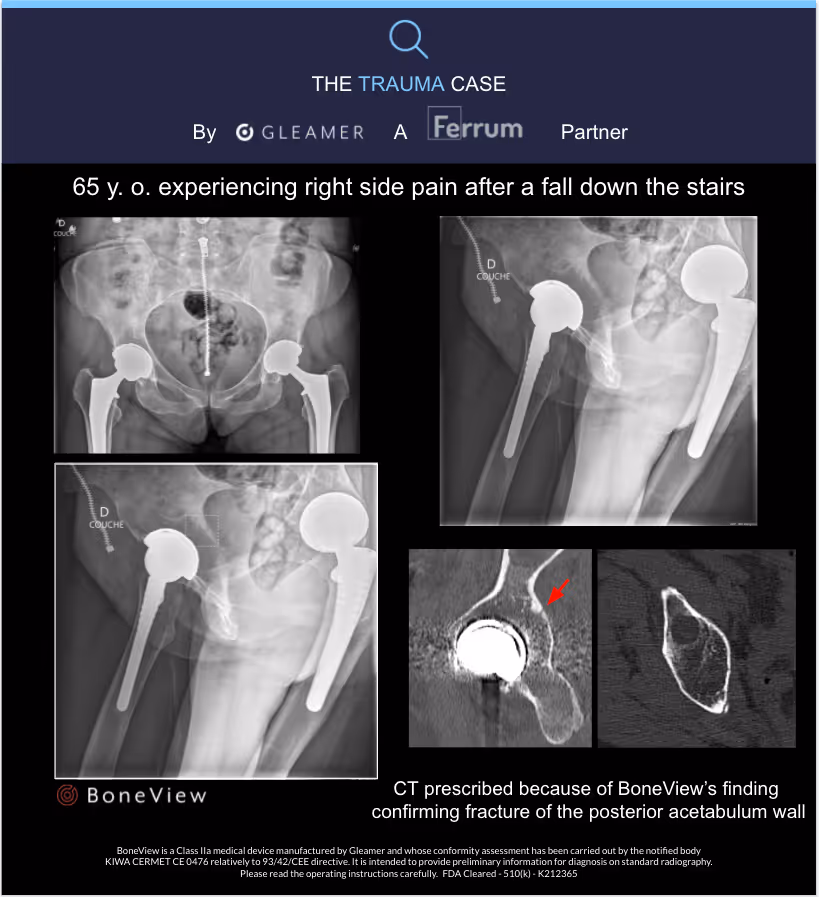

- 65-year-old presented with right-sided pain after falling down the stairs

- Fracture of the posterior acetabular rim detected by BoneView

- Fracture confirmed by a CT